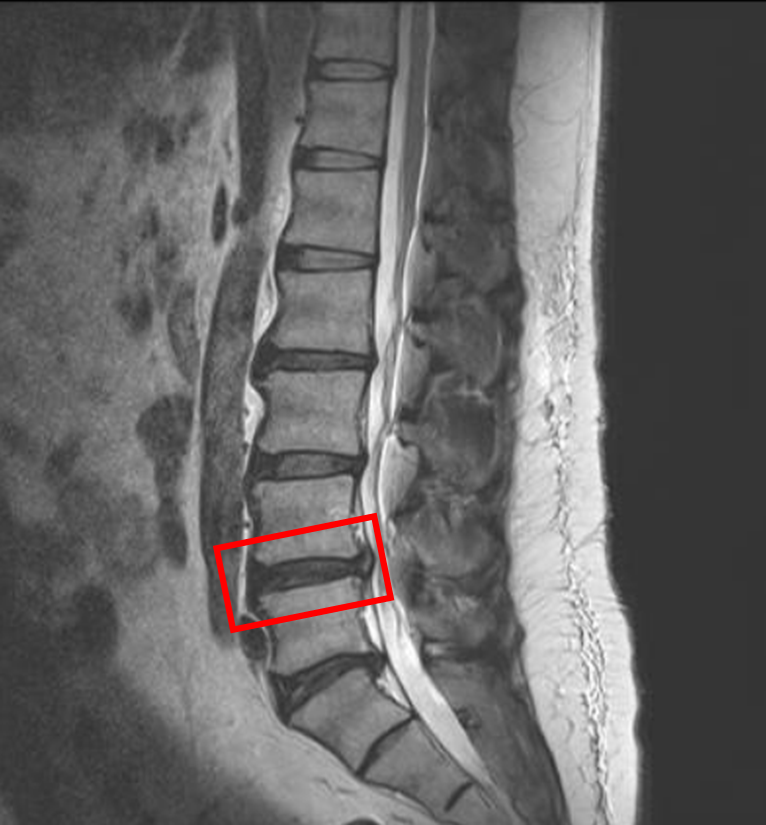

この患者様は赤い枠で示されている箇所(L4/5)に椎間板ヘルニアを認めます。

L5/sは、椎間板変性を認めます。